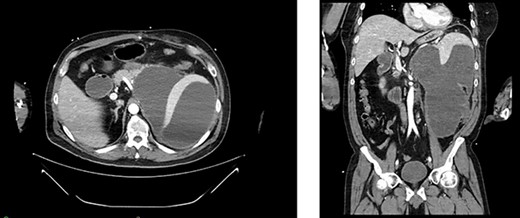

Appearance of effusion in the left retroperitoneal space in transverse (left) and coronal (right) planes on CT; it can be seen encroaching on the spleen; subsequent cytology ruled of malignant effusion.

Two weeks post-resection, the patient was recovering as expected. At 4 weeks post-resection, radiation oncology recommended 7 weeks of intensity-modulated radiation therapy to both the surgical site and at-risk nodes identified on CT. Six weeks post-resection, the patient presented to the ED with nausea and vomiting. Abdominal CT revealed a retroperitoneal effusion at the surgical site (Fig. 3). At this admission, the patient also tested positive for COVID-19, delaying drain placement and his radiation treatments for 2 weeks.